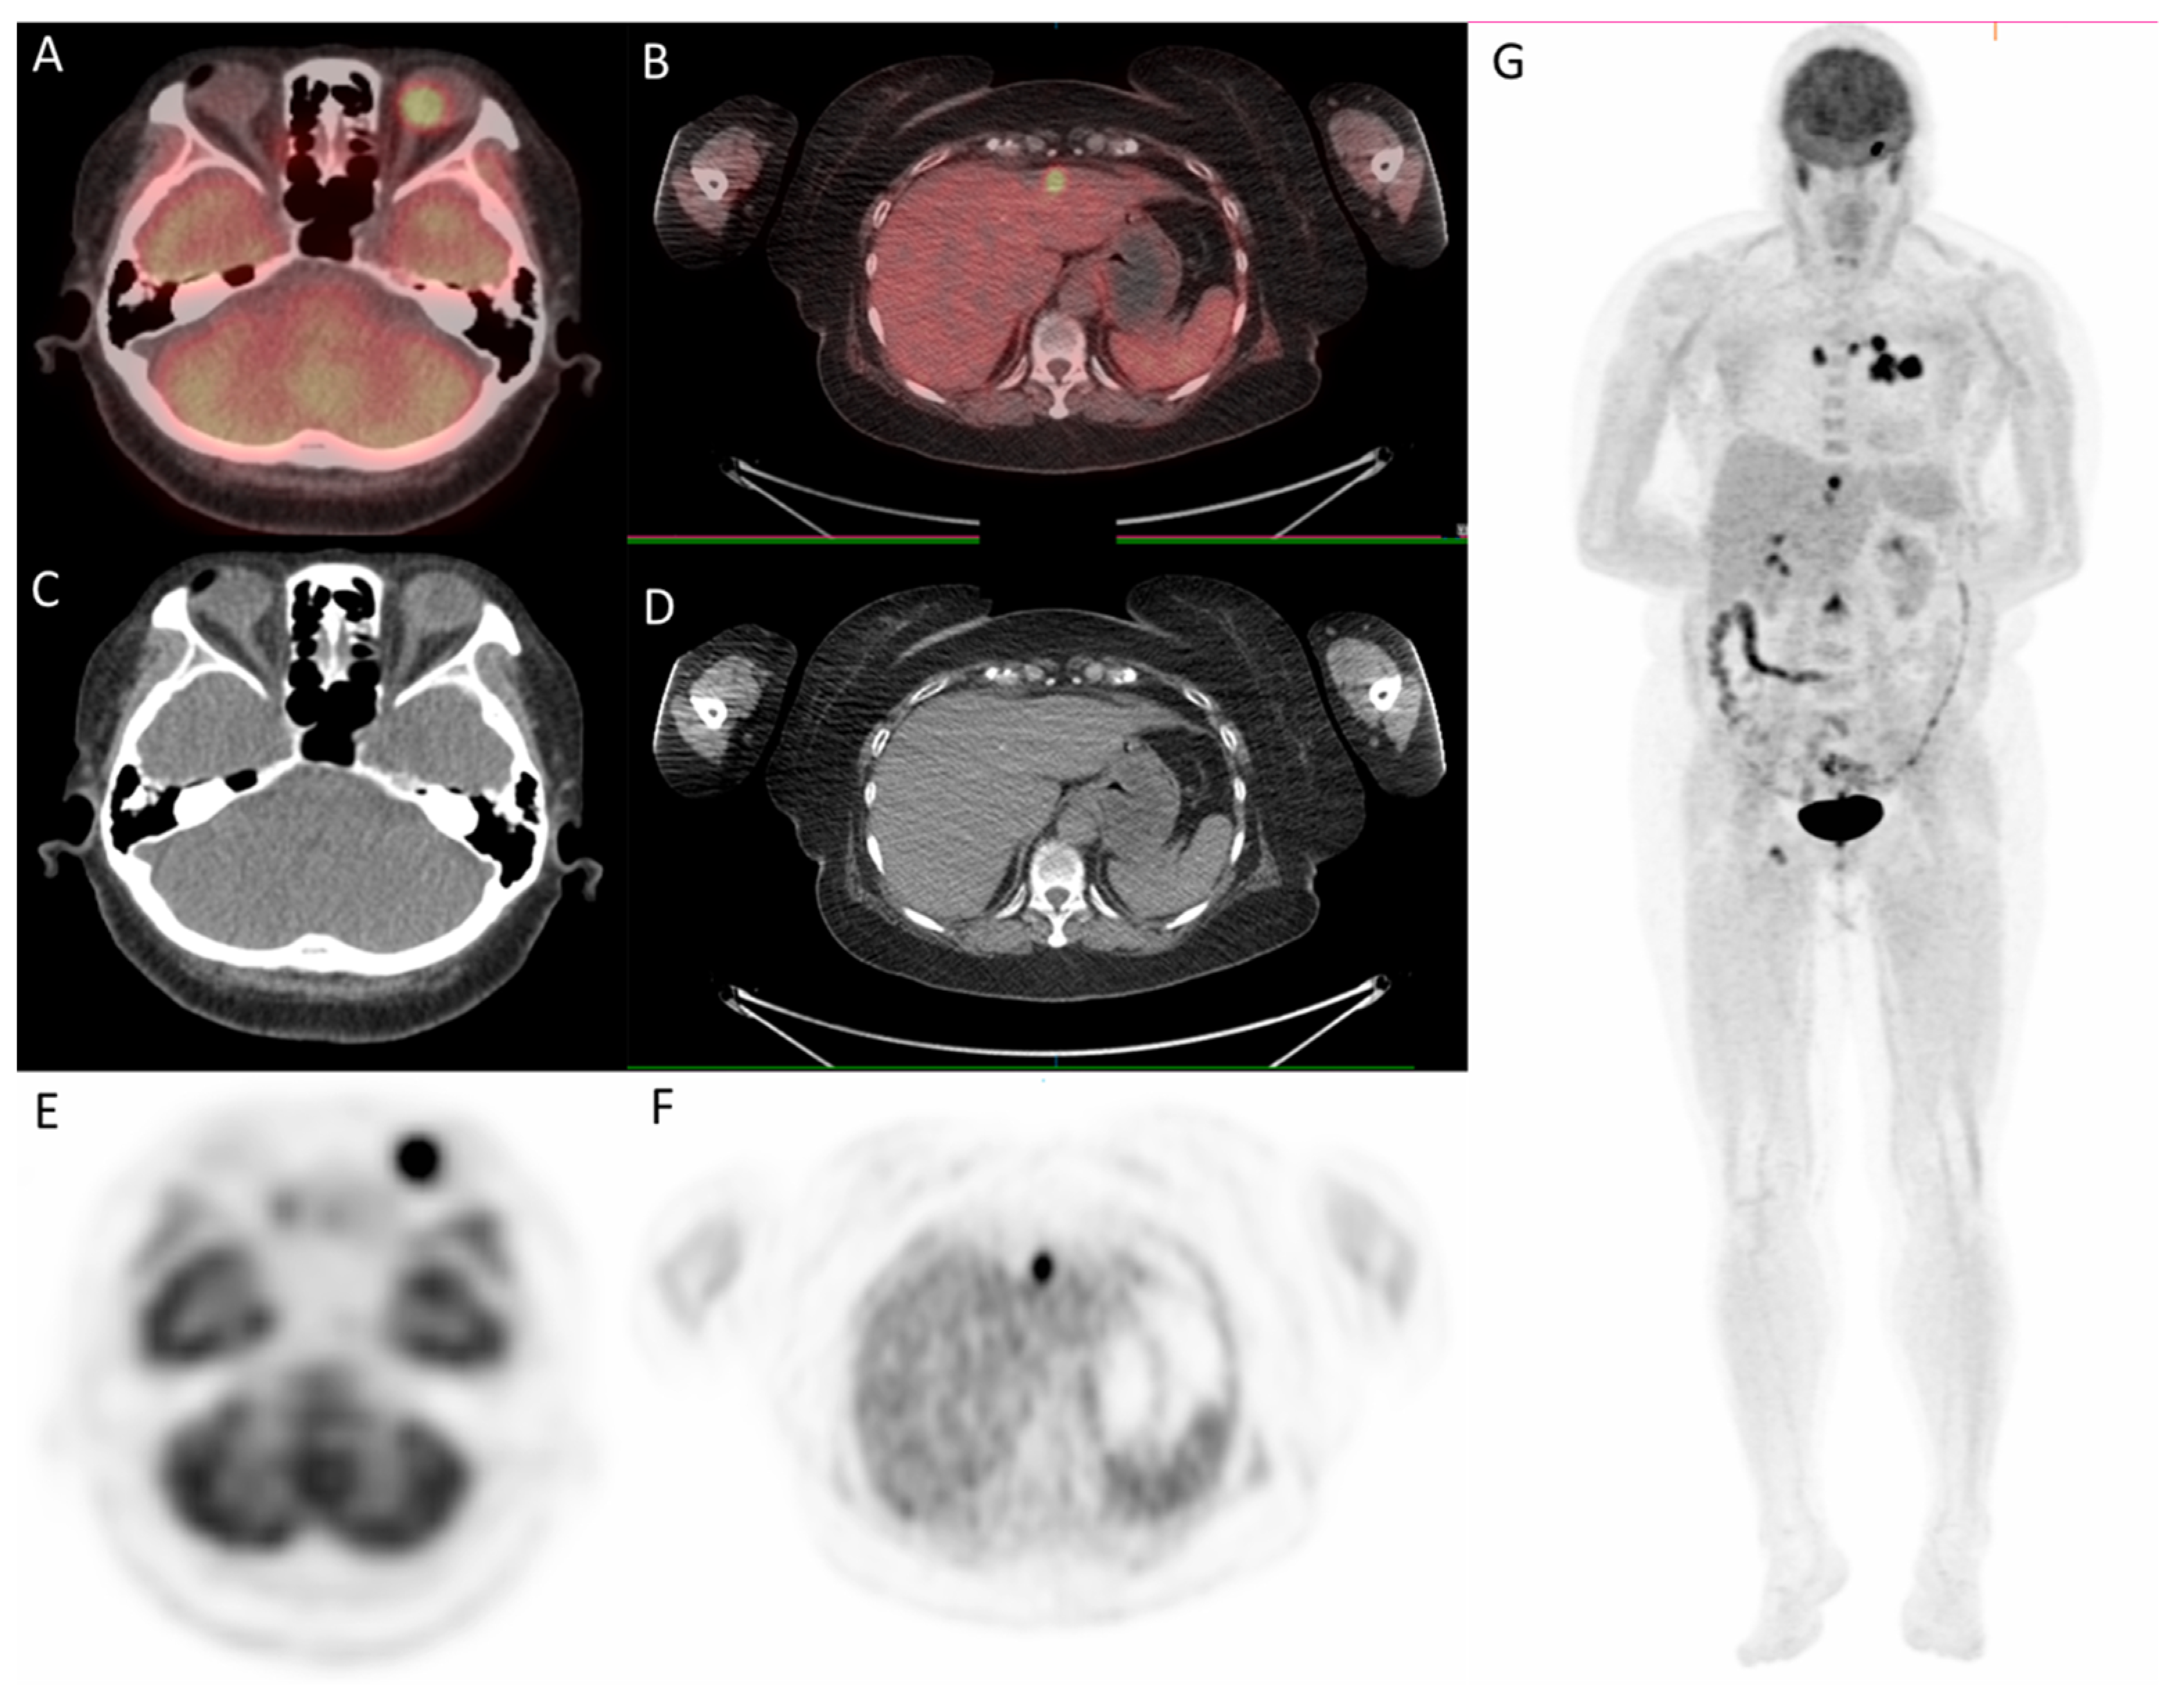

Since the patient had a family history of lung cancer, whole-body positron emission tomography/computed tomography (PET/CT) was suggested; the results showed focal uptake in the left eye with a standardized uptake value (SUV) of 10.8, left upper lung (SUV: 11.5), mediastinum (SUV: 14.8), liver (SUV: 9.6), and bone (SUV: 10) (Figure 5 and Figure 6).

Figure 5.

18F-fludeoxyglucose positron emission tomography/computed tomography (18F-FDG PET/CT) for whole-body evaluation. (A,B) axial fused PET/CT showing focal uptake of the lung and mediastinum, respectively; (C,D) axial CT; (E,F) PET.

Figure 6.

18F-fludeoxyglucose positron emission tomography/computed tomography (18F-FDG PET/CT) for whole-body evaluation. (A,B) axial fused PET/CT showing focal uptake of left eye and liver, respectively; (C,D) axial CT; (E–G) PET. PET/CT.

In the last decade, conventional imaging modalities, such as plain radiography, ultrasound, CT, and magnetic resonance imaging, have been widely used to provide clear structural images of the tumor [16]. PET, which uses short-lived radioisotopes, such as fluorine-18 to label glucose, can detect malignancy and be used for staging, restaging, or monitoring treatment responses [17]. PET combined with CT provides simultaneously high sensitivity of tracer distribution and high precision of localization, facilitating the detection of tumor sites in patients with choroid metastasis. In the present case, PET/CT scan was utilized early for detection of tumor sites, and it highlighted multiple uptakes in the left eye, left upper lung, mediastinum, liver, and bone. In addition to providing useful clues to the possible primary tumor sites, it was fast and efficient.